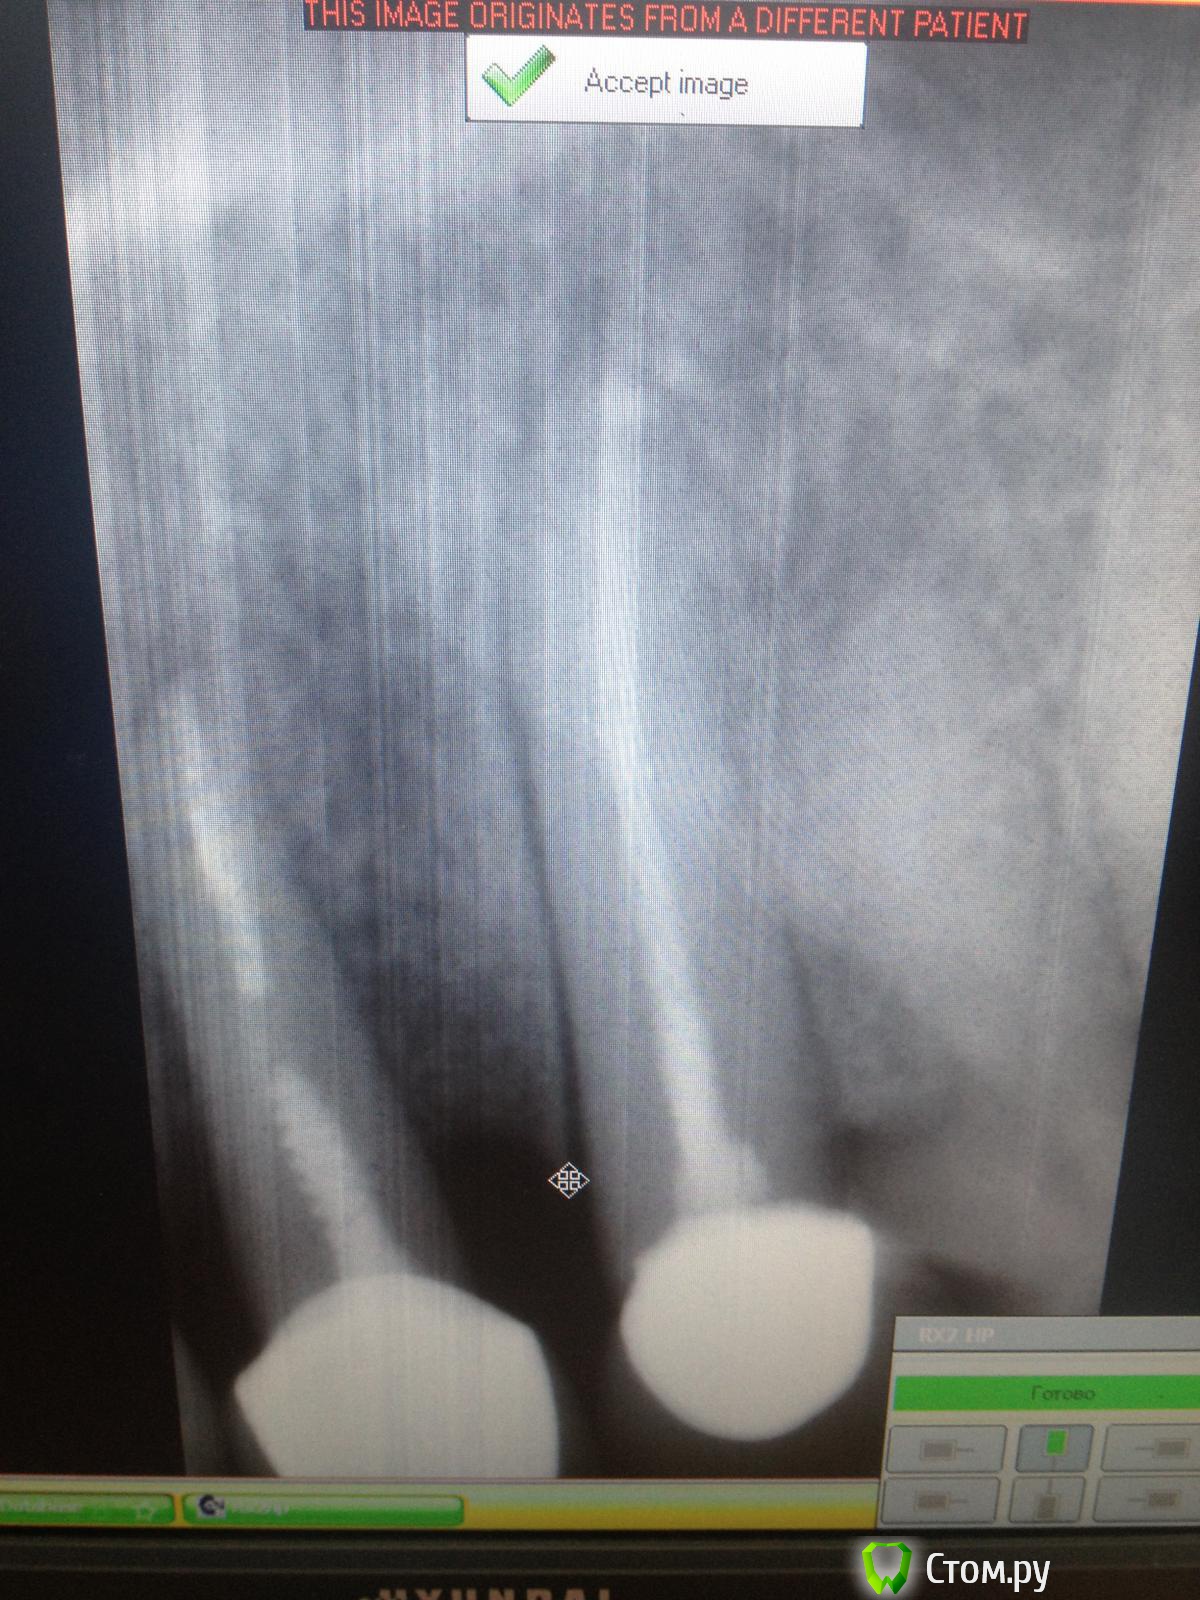

SergioS Опубликовано 26 февраля, 2014 Поделиться Опубликовано 26 февраля, 2014 Режь!Если гной - дренаж, Если нет - гистология +100)))И снимок бы поинформативнее! Ссылка на комментарий

шахтер Опубликовано 26 февраля, 2014 Поделиться Опубликовано 26 февраля, 2014 разбитые апексы, грязное эндо 22,23 Ссылка на комментарий